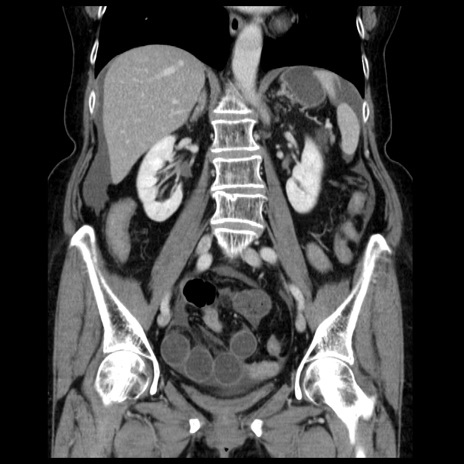

症例13(冠状断像)

【症例】70歳代女性

【主訴】腹痛、嘔吐

【現病歴】15時間程前(昨晩)より腹痛あり。今朝になっても症状の改善なく、嘔吐あり。腹痛も増悪あり、救急外来受診。

【既往歴】子宮癌全摘術後

【身体所見】意識清明、BP 121/72mmHg、P 74bpm、SpO2 100%(RA)、腹部:平坦・軟、腸雑音ほぼ聴取せず。下腹部・心窩部・臍左上に圧痛あり。反跳痛なし。

【データ】WBC 10600、CRP 0.15